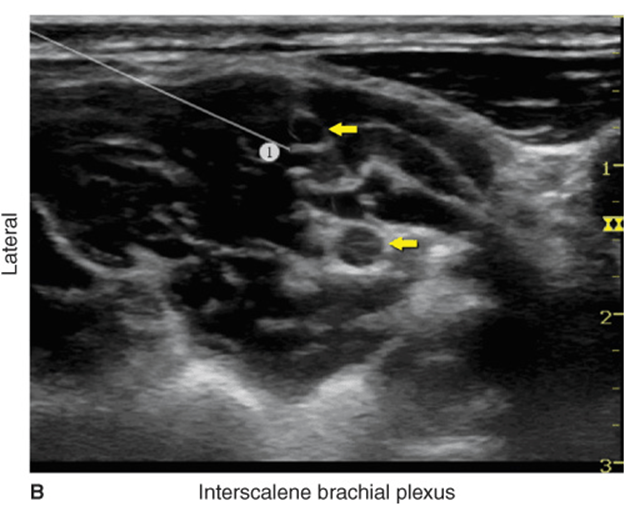

The needle is then inserted in-plane toward the brachial plexus, typically in a lateral-to-medial direction (Figure 29-7), although medial-to-lateral needle orientation also can be chosen if more convenient. As the needle passes through the prevertebral fascia, a certain “give” is often appreciated. When nerve stimulation is used (0.5 mA, 0.1 msec), the entrance of the needle in the interscalene groove is often associated with a motor response of the shoulder, arm, or forearm as another confirmation of the proper needle placement. After a careful aspiration to rule out an intravascular needle placement, 1 to 2 mL of local anesthetic is injected to document the proper needle placement (Figure 29-8A). Injection of several milliliters of local anesthetic often displaces the brachial plexus away from the needle. An additional advancement of the needle 1 to 2 mm toward the brachial plexus may be beneficial to assure a proper spread of the local anesthetic (Figure 29-8B). Whenever the needle is further advanced, or multiple injections used, assure that high resistance to injection is absent to decrease the risk of an intrafascicular injection. When injection of the local anesthetic does not appear to result in a spread around the brachial plexus, additional needle repositions and injections may be necessary.

FIGURE 29-7. (A) Transducer placement and needle insertion. (B) Position of the needle (1) for the interscalene brachial plexus block using an in-plane approach. The needle tip is seen in contact with the superior trunk of the brachial plexus (yellow arrows); this always results in high injection pressure (>15 psi)—indicating that the needle should be withdrawn slightly away from the trunk.